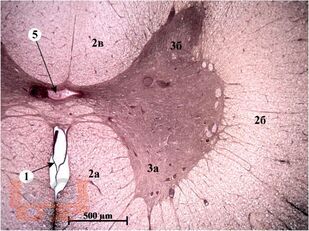

Учебное пособие состоит из оригинальных цветных фотографий, каждая из которых сопровождается описанием и указанием учебных элементов.

Описание фотографий соответствует принятой в 2009 г. Международной терминологии по гистологии и цитологии. Каждый раздел завершается перечнем вопросов, которые позволяют осуществлять самоконтроль усвоения изученного материала. Разделы структурированы в соответствии с рабочей программой дисциплины «Частная морфология: анатомия, гистология», утверждённой в СибГМУ.